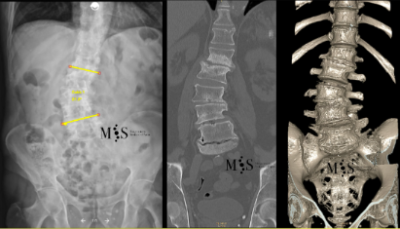

Escoliosi degenerativa

L'escoliosi és la deformitat de la columna vertebral en el pla frontal. La escoliosis pot ser congènita (des del naixement) o degenerativa (es pot adquirir amb l’edat). La degeneració progressiva dels discs intervertebrals (per l’edat, el pes i l’activitat) pot comportar que la columna es deformi amb els temps i acabi generant-se una escoliosi degenerativa o "de novo" (perquè ha aparegut de forma "nova", al contrari que en l’escoliosi congènita que sempre a estat allà des del naixement).

Les escoliosis provoquen una deformitat progressiva de l’esquena i el pacient no pot caminar recte. A més, les escoliosis poden provocar dolor lumbar i a tota l’esquena. També és possible que per la deformitat hagi arrels nervioses pinçades pels discos degenerats, resultant en un dolor irradiat per una o dues cames.